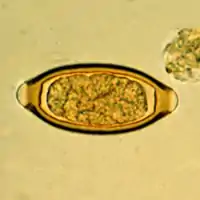

Egg of Trichuris trichiura